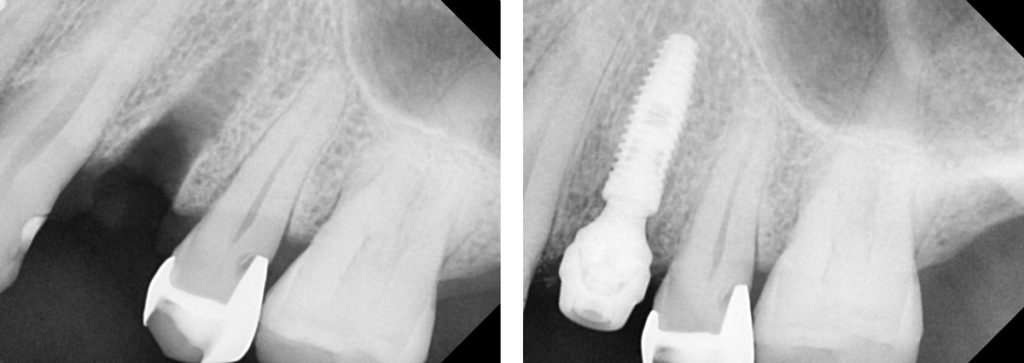

Un implante dental sirve para reemplazar un diente perdido, se le llama la tercera dentición, la primera es la dentición del niño, la segunda es la del adulto. Un implante dental es una forma de recuperar la función masticatoria, deglución, fonación y confianza al sonreír de las personas.

En general los implantes dentales requieren un proceso de planeación minuciosa en una tomografía dental , así como guiarlos en base a la corona dental que llevará fija al tornillo, de esta forma el pronóstico será más favorable a largo plazo.

El diente definitivo que va fijo al implante se coloca generalmente 3 meses posterior a la colocación del tornillo en el hueso, este periodo de tres meses es el que biológicamente tardará el implante en integrarse a la superficie del hueso, el proceso de rehabilitación del implante es de aproximadamente 3 citas, la primera consiste en destapar la conexión del implante y formar un perfil en la encía, la segunda cita se tomará la impresión del implante y de la encía ya formada a su alrededor, la tercera cita se medirá una corona idéntica a la que podría ser la final , si la anatomía de la corona definitiva corresponda a los espacios y a la oclusión del paciente se envia a fresar en un material definitivo como puede ser zirconia y se coloca sobre el implante para así dar por terminado el proceso de rehabilitación.